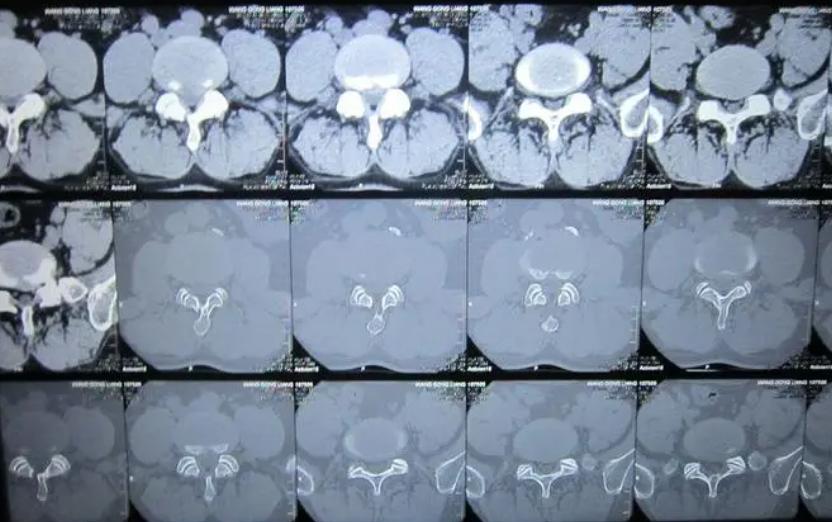

一位来自甘肃的47岁男性患者,通过检查确诊为腰4/5、腰5/骶1椎间盘膨出并腰5/骶1椎间盘突出,硬膜囊前缘受压,双侧椎间孔狭窄,局部椎管狭窄,腰3/4椎体相对缘许莫氏结节。找到我时,自述说腰部疼痛以及大腿右后侧疼,还有右下肢疼痛麻木,当地医院让他必须做手术才行,但他不想做,于是就找了很多医生咨询。